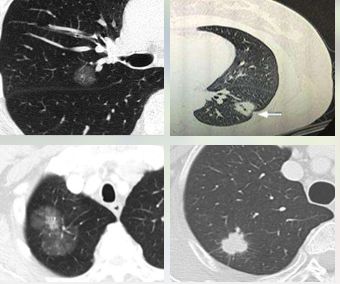

唐小军教授提到,对于肺结节手术,要根据肺结节的大小、位置、数量及分布来选择具体手术方式。

1.楔形切除:

结节位于肺周边部分;

结节直径<2cm的磨玻璃结节;

患者年龄或身体情况不能耐受更大范围肺切除或更复杂的手术方式;

需要获取病理诊断及基因检测所需要组织,而其他手段无法实现。

2.肺叶切除:

结节位于肺叶中心区域,临近肺叶的支气管和血管;

结节直径>2cm的确诊为肺癌的结节;

胸膜受侵犯的肺癌结节;

术中病理检查证实有肺门/纵隔淋巴结转移的肺癌;

同一肺叶有多个确诊或拟诊为肺癌的结节。

3.解剖性肺段切除:

结节<2cm,且实性成分<50%,未侵犯胸膜;

没有肺内/肺门以及纵隔淋巴结转移;

与肺叶的支气管和肺血管距离>2cm;

不能耐受肺叶切除的部分患者。